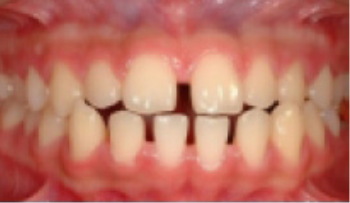

• 치간 공극 치아 사이가 벌어짐.

Before

After